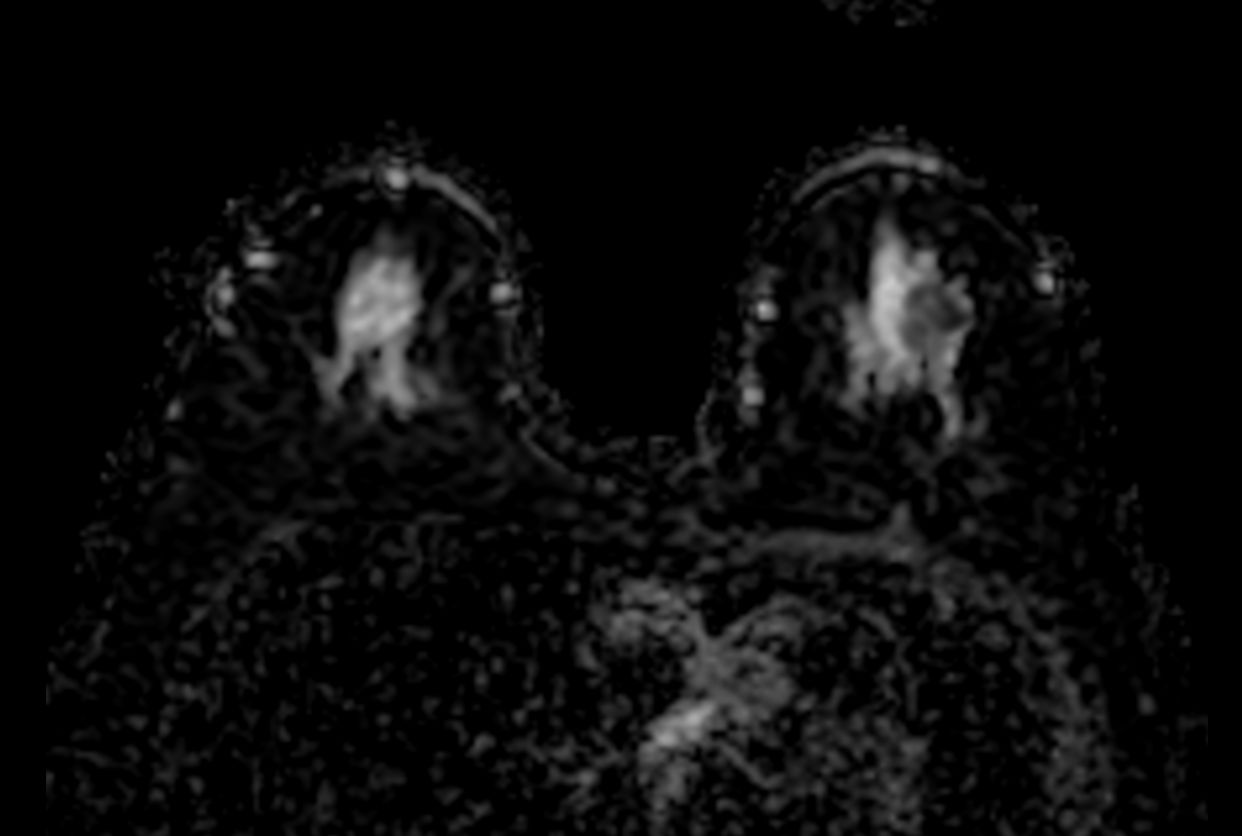

Diffusion (b750)